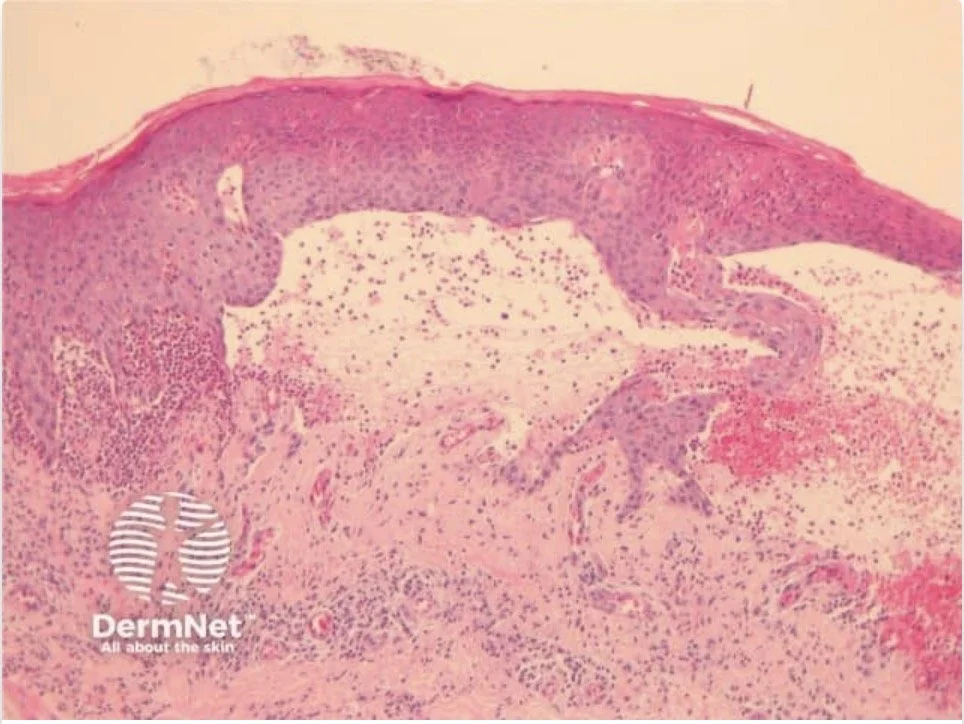

HISTOLOGY (H&E)

H&E by itself can’t give you a full diagnosis but it can give you some clues to the diagnosis based on:

Level of split:

• Subcorneal

• Intraepidermal

• Subepidermal

Nature of inflammatory infiltrate:

• Neutrophils

• Eosinophils

• Lymphocytes

• Cell-poor

The acantholysis in PV occurs just above the basal layer of the epidermis, leading to a suprabasilar split

https://dermnetnz.org/topics/pemphigus-vulgaris-pathology